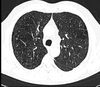

Q

Q tipo de enfisema es

A

Centrolobulillar